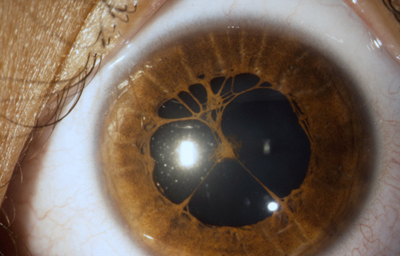

Colobomas típicos con diferentes grados de defecto en el desarrollo

Colobomas Atípicos.

Archivo Fotográfico Dr. Francisco Barraquer

Archivo Fotográfico Dr. Francisco Barraquer